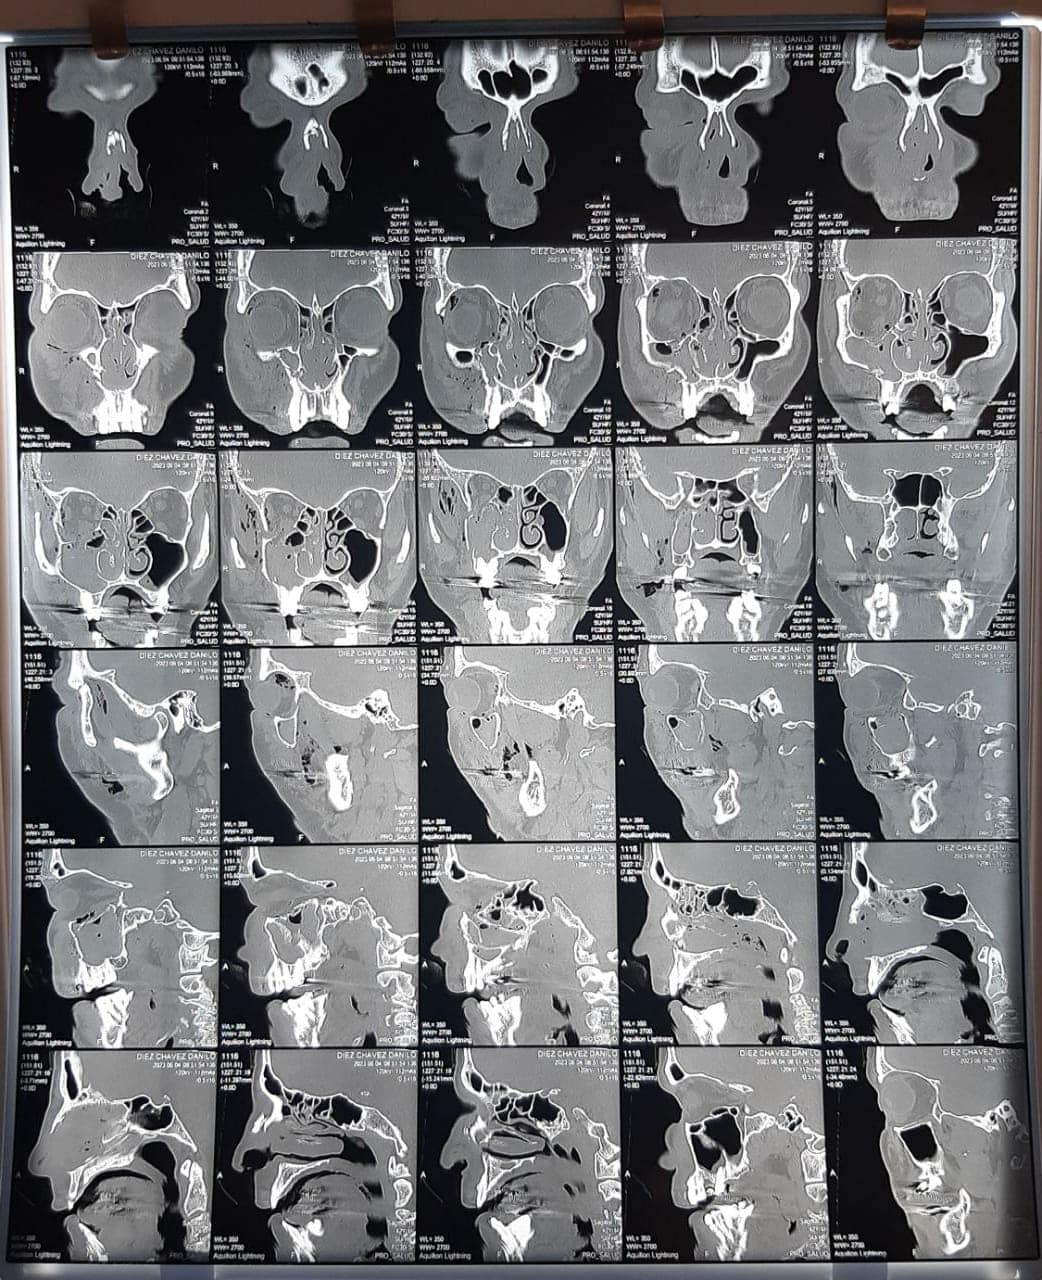

Según la denuncia hecha ante la policía Jesús Danilo Diez fue golpeado por detrás por Fabio Chávez identificado como peleador de MMA. Debido a los golpes, la víctima acabó con la nariz y el pómulo partido, su cuadro se agravó al presentar coágulos de sangre en el cerebro por las patadas recibidas en la cabeza.

El denunciado de nombre FABIO CHAVEZ, de apodo el tanque un boxeador profesional de la M.M A le ofreció pelear sin razon alguna y en descuido con una manopla en su mano le agrede dándole puñetes en su rostro, quebrándole la nariz y el frontal del pómulo izquierda, al caer al piso recibió patadas en su cabeza del denunciado y otros N.N. causándole inflamación en su cerebro, y coágulos de sangre, por esta agresión física del sindicado y otros N.N. quienes agredian a cualquier persona por el lugar.